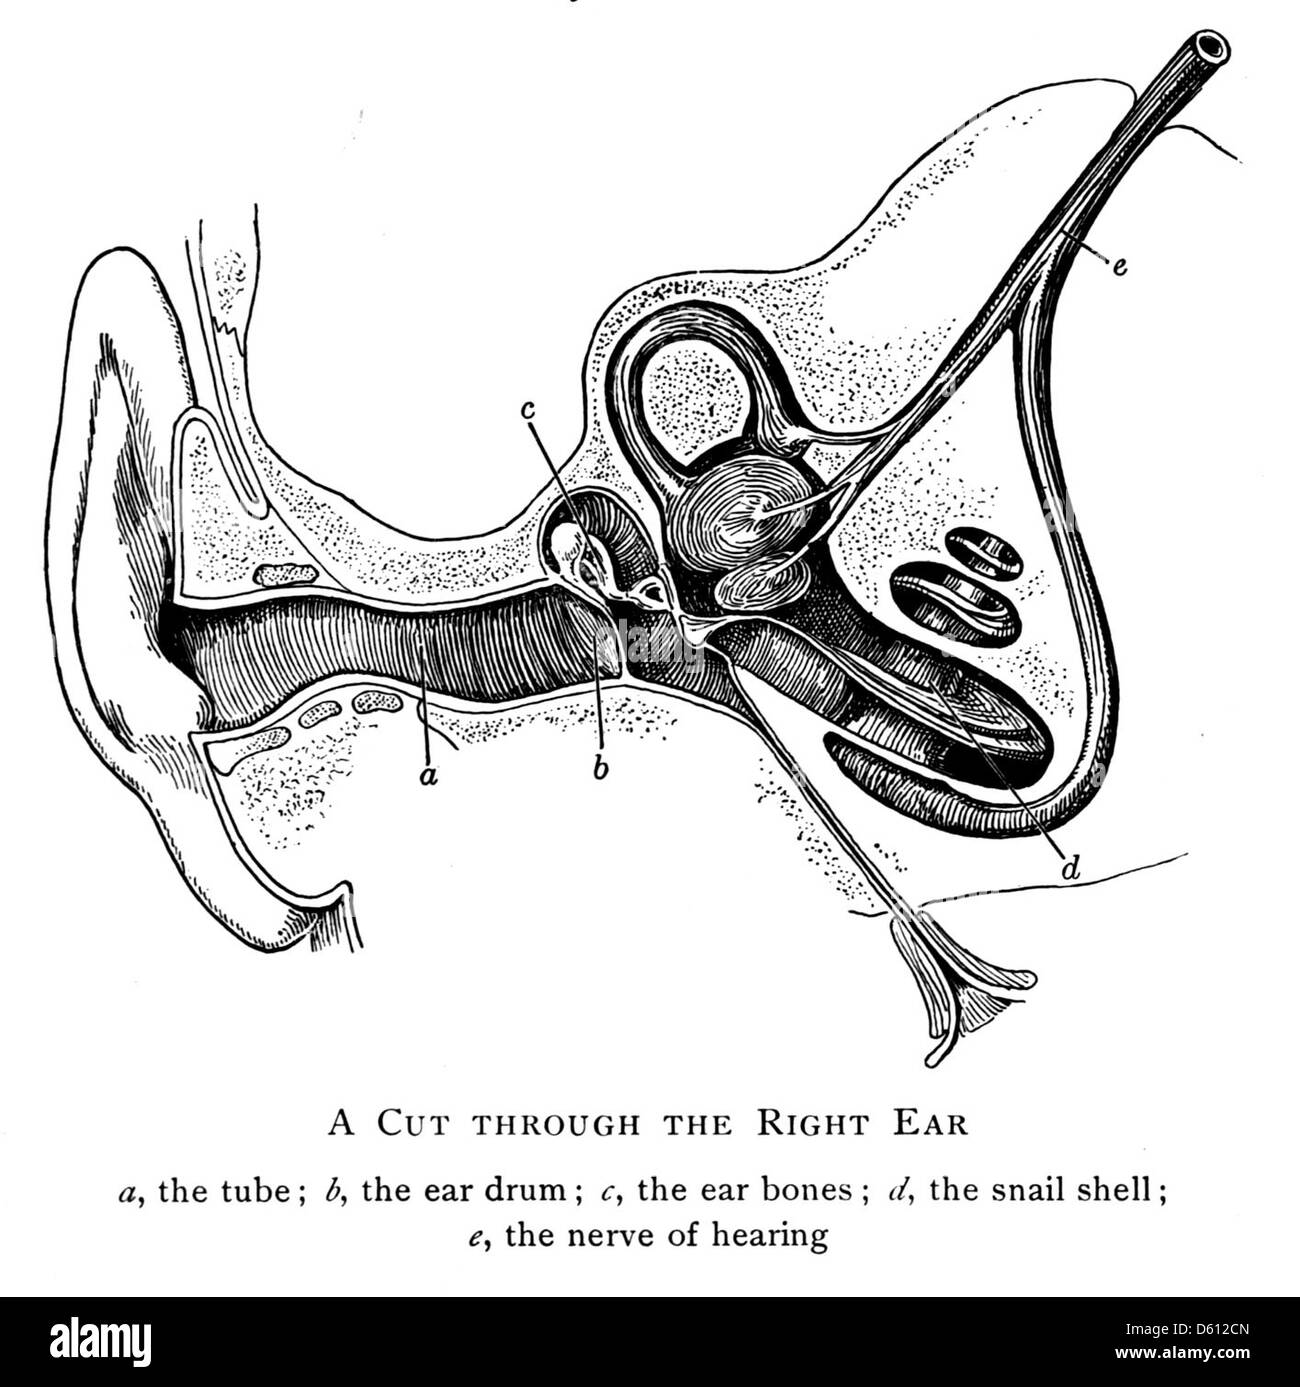

Une illustration de 1906 tirée de « Good Health », représentant l'anatomie de l'oreille humaine. Le diagramme met en évidence les structures de l'oreille, fournissant une référence scientifique pour la compréhension de la biologie humaine. Banque D'Imageshttps://www.alamyimages.fr/image-license-details/?v=1https://www.alamyimages.fr/photo-image-une-illustration-de-1906-tiree-de-good-health-representant-l-anatomie-de-l-oreille-humaine-le-diagramme-met-en-evidence-les-structures-de-l-oreille-fournissant-une-reference-scientifique-pour-la-comprehension-de-la-biologie-humaine-55342917.html

Une illustration de 1906 tirée de « Good Health », représentant l'anatomie de l'oreille humaine. Le diagramme met en évidence les structures de l'oreille, fournissant une référence scientifique pour la compréhension de la biologie humaine. Banque D'Imageshttps://www.alamyimages.fr/image-license-details/?v=1https://www.alamyimages.fr/photo-image-une-illustration-de-1906-tiree-de-good-health-representant-l-anatomie-de-l-oreille-humaine-le-diagramme-met-en-evidence-les-structures-de-l-oreille-fournissant-une-reference-scientifique-pour-la-comprehension-de-la-biologie-humaine-55342917.htmlRMD612CN–Une illustration de 1906 tirée de « Good Health », représentant l'anatomie de l'oreille humaine. Le diagramme met en évidence les structures de l'oreille, fournissant une référence scientifique pour la compréhension de la biologie humaine.